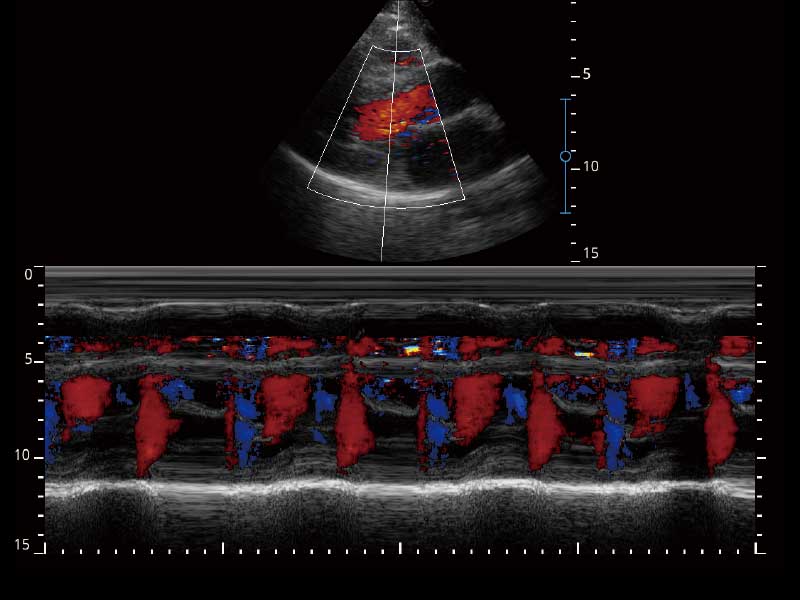

E2便携式彩色多普勒超声诊断系统采用专业的超声技术平台、高度集成化的硬件模块和结构设计、简便的操作流程、多探头接口设计,兼顾了优质图像、轻便机身以及台便两用的临床使用需求。

• 高端成像技术

μ-Scan微米成像、空间复合成像、高分辨率血流成像。

临床图